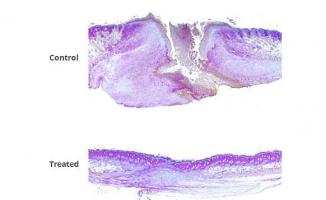

Actualité publiée il y a 6 années 8 moisPLAIES CHRONIQUES ou TRAUMATIQUES : Une association thérapeutique qui révolutionne la cicatrisation